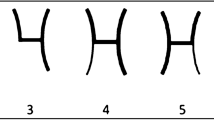

Despite the AComA’s great morphological variability and its clinical impact, no study summarizes results for every possible variant. The typical AComA had a 67.3% PP (Type 1), and therefore the atypical patterns occurred with 37.2% (Types 2–8). The atypical patterns will be presented with decreasing frequency. Specifically, the commonest variant was estimated as the AComA hypoplasia with an 8% PP (Type 2). Type 3 was considered the artery’s absence, where it is possible to identify two different morphological types. AComA absence with the two ACAs fused (azygos ACA) had a 5.9% PP (Type 3). Whereas AComA absence with the two ACAs coursed in parallel was estimated with a 4.6% PP (Type 5). An artery is considered fenestrated when its arterial lumen splits into two distinct channels that eventually fuse along its course [36]. Sometimes it is mistaken for duplication, which is defined as the occurrence of two distinct arteries with separate origins [36]. The AComA fenestration was estimated with a 5% PP (Type 4). The AComA could be presented in different shapes (V-shaped, Y-shaped, and plexiform). All possible shapes were considered as AComA was differently shaped with a 4.5% PP (Type 6). In addition, other rarer variants could be present. AComA duplication is estimated at a 4.3% PP (Type 7). A branch emanating directly from the AComA can be identified, which represents an embryological remnant. The MACC persistence had a 2.3% PP (Type 8). The AComA can be identified triplicated in 0.7% (Type 9). Hence, the current meta-analysis proposes a simplified classification system of the AComA morphological variability, by using the PP of its variant in decreasing order (Fig. 12). Nevertheless, it is important to mention some significant results from the meta-analysis subgroup analysis. The typical pattern had a statistically significant difference in a geographic region (America: 82%; Europe: 67%; Asia: 58%), however, only one study was included in the American region (minimum four studies per subgroup [62]). The AComA absence had an interesting statistically significant difference between the studies’ methods. The cadaveric studies’ PP was estimated at 2%, while the imaging studies had a PP of 13% (p < 0.0001). This relationship could be attributed to the difficulty in differentiating small arteries (small diameter and length) in imaging studies. Hence, a small AComA could be misdiagnosed as AComA absence. In cases where there is a hemodynamic imbalance between the ACAs on both sides and no flow through the AComA, it will not be visible on neuroimaging. Another significant methodological difference between the studies was identified in AComA duplication. The cadaveric studies had a 6.5% PP, while the imaging studies PP was 0.9% (P < 0.0001). This relationship could be attributed to the difficulty of diagnosing a second AComA that may be quite small in diameter, during an imaging study. Nevertheless, AComA absence, fusion, duplication, and triplication were identified with a statistically significant difference between geographic regions, whereas only one study was included in the American region (minimum of four studies per subgroup [62]).

Schematic representation of the proposed classification of the anterior communicating artery (AComA) variants based on their frequency, in decreasing order. Type 1 (typical); Type 2 (hypoplastic); Type 3 (absence with ACAs fused); Type 4 (fenestration); Type 5 (absence with ACAs in parallel); Type 6 (different shaped); Type 6 A (Y-shaped); Type 6B (V-shaped); Type 6 C (plexiform); Type 7 (duplication); Type 8 (median artery of corpus collosum-MACC); Type 9 (triplication)